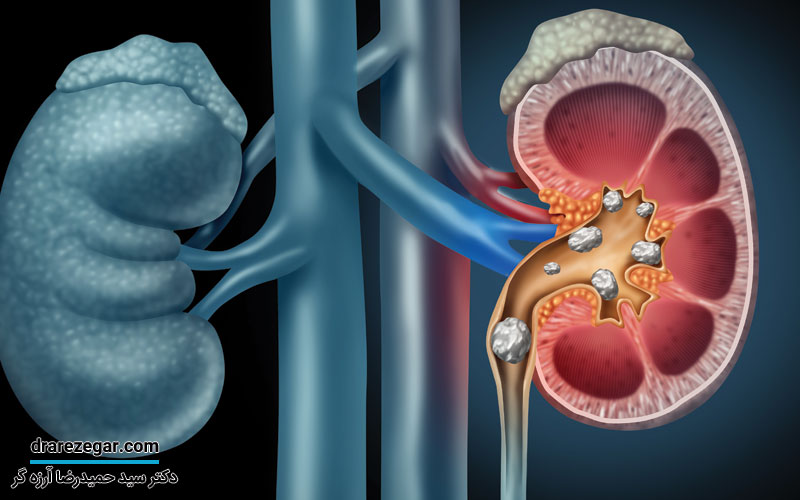

علائم وجود سنگ کلیه

سنگ کلیه معمولاً با علایم شدیدی بروز می کند اما در برخی اوقات نیز بی علامت بوده و فرد فقط یک درد مبهم در بخش پهلو احساس خواهد کرد؛ همچنین می توان از مواردی مثل خون در ادرار، عفونت های ادراری عود کننده به وجود سنگهای کلیه پی برد. در موارد شدید درد سنگ کلیه مانند درد زایمان است؛ زیرا در اثر حرکت سنگ و گیر افتادن آن در حالب بروز می کند که در چنین حالتی ورم و اتساع کلیه ها رخ می دهد و بیمار همراه با درد علائمی مثل تهوع و استفراغ خواهد داشت.

توجه داشته باشید که هر چقدر سنگ های کلیه کوچک تر باشند، علامت و نشانه های آن ها شدیدتر است و بالعکس هر چه سنگ بزرگ تر باشد حرکت آن کم تر بوده و بیمار درد کمتری را احساس می کند. سنگ های بزرگ معمولاً در چکاپ های دوره ای کشف می شوند و بیمار هیچگونه علائمی را احساس نخواهد کرد. اما این وضعیت به عنوان قاتل خاموش کلیه شناخته می شود. عفونت های ادراری مقاوم و عود کننده یکی از علایم وجود سنگ های کلیه در سیستم ادراری هستند که باعث ایجاد باکتری به عنوان سنگر دفاعی می شوند. در چنین شرایطی علایم بیمار با مصرف آنتی بیوتیک بهبود می یابد اما با قطع آن عفونت دوباره عود می کند.